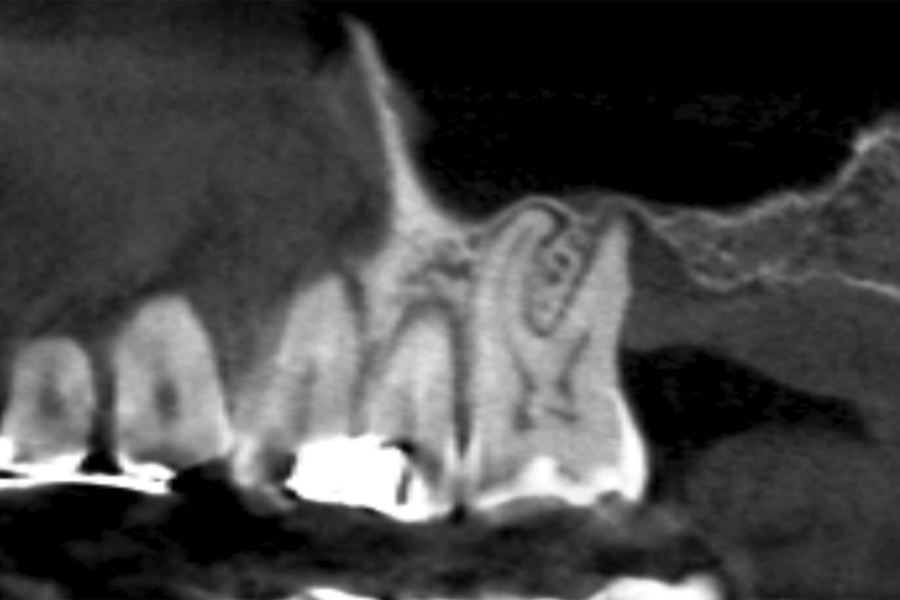

Figures 2-19 show one of the cases included in the study.

Patients attend subsequent check-ups performing a control Cone-Beam after 5 months (before loading the implant) and after one year of the load, performing a new measurement in these images to analyse the bone gain and the maintenance of the same. In these check-ups, data are collected on prosthetic complications or crestal bone loss in these patients, as well as possible failures.

The mean height of the residual bone volume was 3.1 mm (+/- 0.3 mm with a range of 3-4 mm). In all cases, transcrestal sinus elevation was performed, with particulate autologous bone obtained from milling the neo alveolus generation zone for implant insertion, being the average of this elevation above the apex of the implant of 2.8 mm (+/- 0.99 range 1.9 -5 mm). In the CT control scan after one year of inserting the studied implants, the bone gain achieved was maintained, no decrease in the volume gained was observed, only three cases showed a decrease of between 0.4 and 0.5 mm of the initial volume at the end (Table).